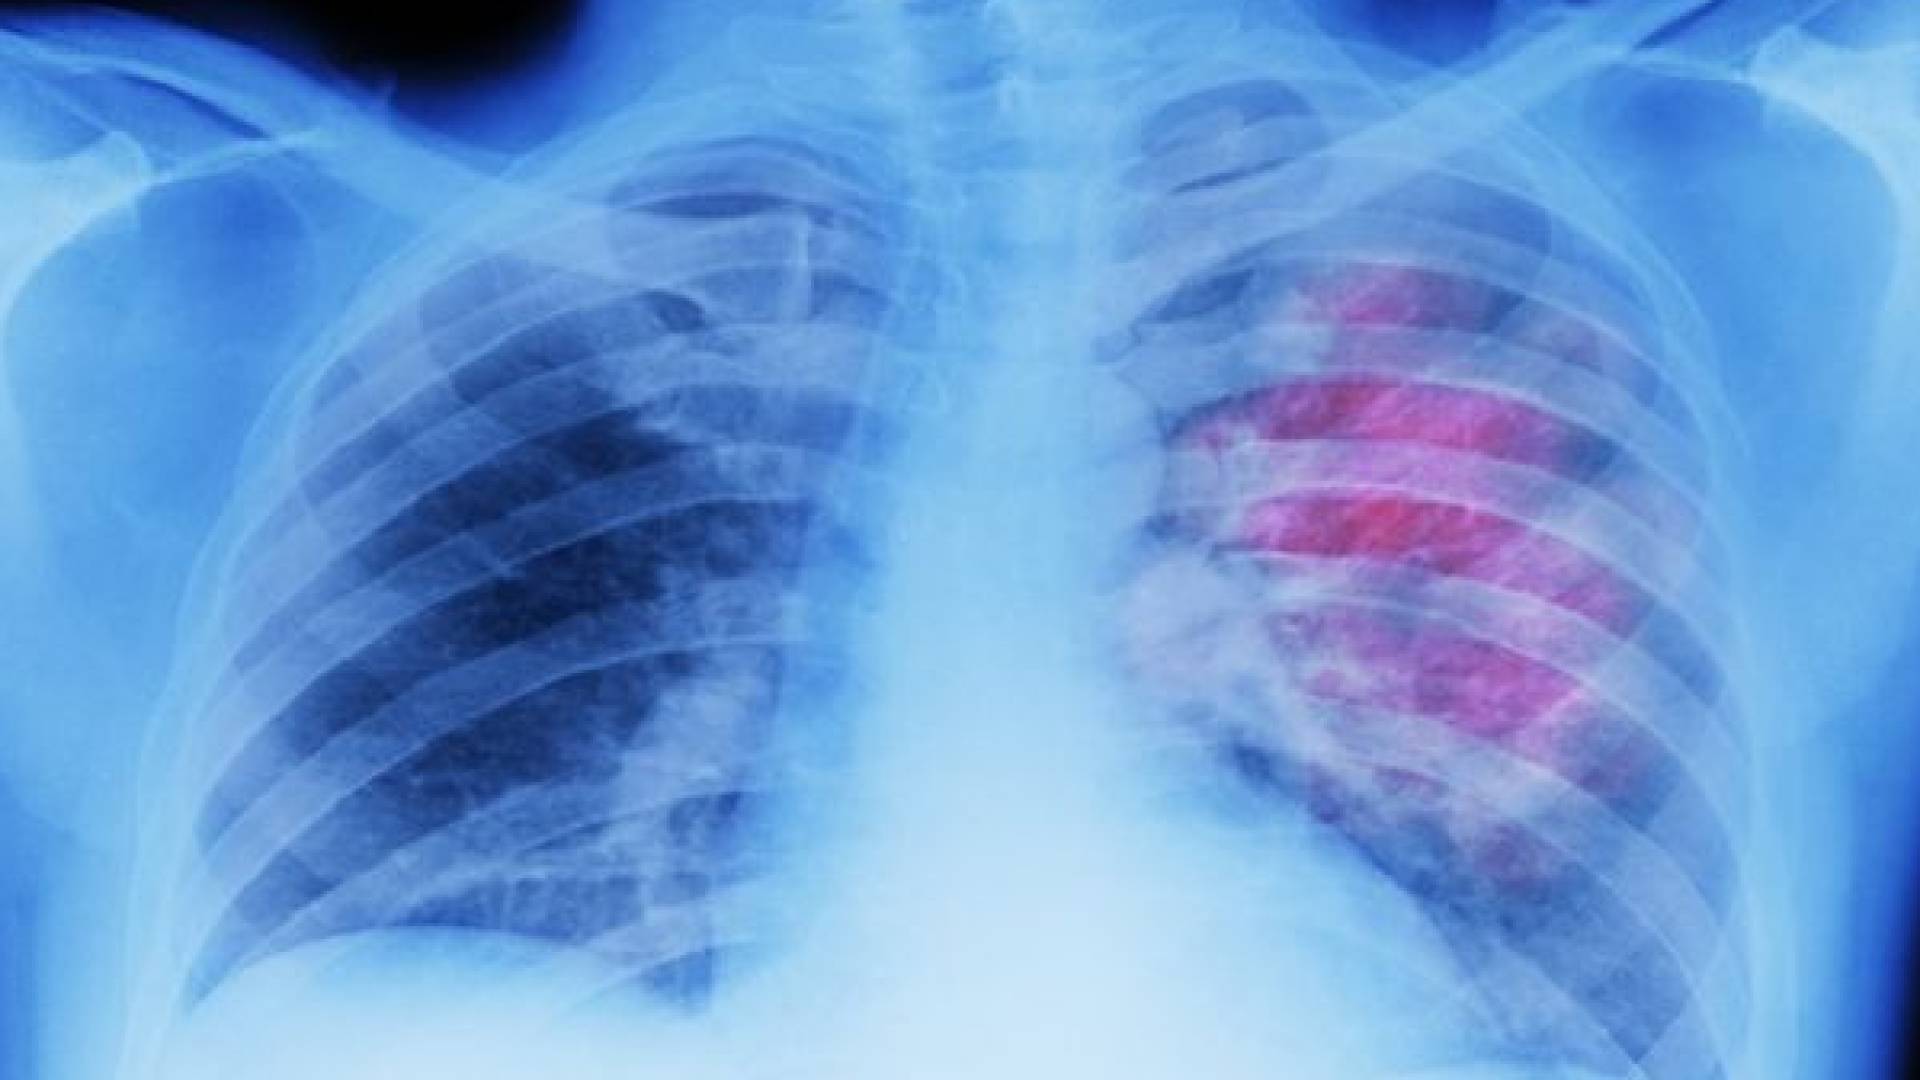

ويتوقف التنفس أثناء النوم عندما تسترخي العضلات في المجاري التنفسية، إلى درجة إعاقتها بالكامل، ليتوقف التنفس مدة 10 ثوان على الأقل. ويمكن علاج الحالة عن طريق الضغط الهوائي الإيجابي المستمر، حيث يمكن ارتداء قناع خاص أثناء النوم، للحفاظ على المجاري التنفسية بحالة جيدة.

ويعد انخفاض قراءات الأوكسيجين في الدم ليلا، أحد العلامات الرئيسية لتوقف التنفس أثناء النوم. ويرجع ذلك إلى انخفاض كمية الأوكسيجين التي تدخل إلى مجرى الدم.